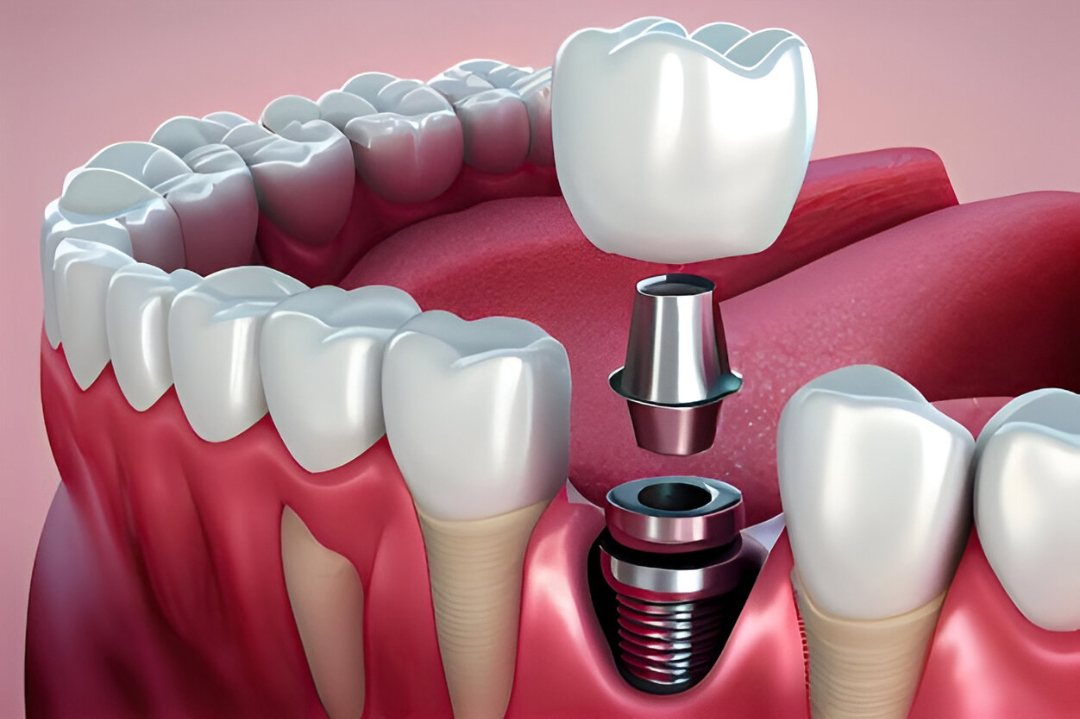

Dental Implants

3D imaging, digital x-rays